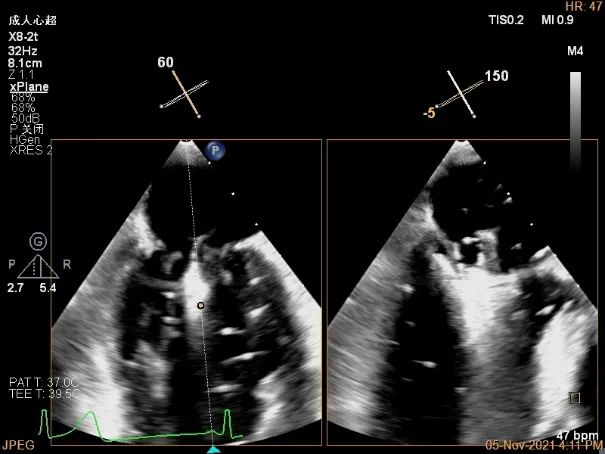

3D视图下进夹子并建立trajectory

3D视图打开夹子

3D视图下调Rotate,主要定位2区

X-plane:下夹子尝试捕获2区脱垂瓣叶

Gripper,前叶捕获长10.1mm,后叶捕获长度8.9mm